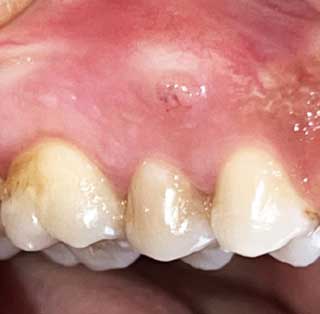

Le diagnostic de l’abcès parodontal est principalement clinique. Il est caractérisé par la présence d’une élévation ovoïde dans la gencive le long de la partie latérale de la racine (3).

La gencive est souvent rouge, œdémateuse, lisse et douloureuse à la palpation (11). Au sondage, la présence d’une poche parodontale saignante est de règle (Fig 1a). Une suppuration et une augmentation de la mobilité́ dentaire peuvent être observées (14).

Fig 1a : Abcès parodontal en lingual de la 41 montrant un œdème avec présence de poche parodontale. |